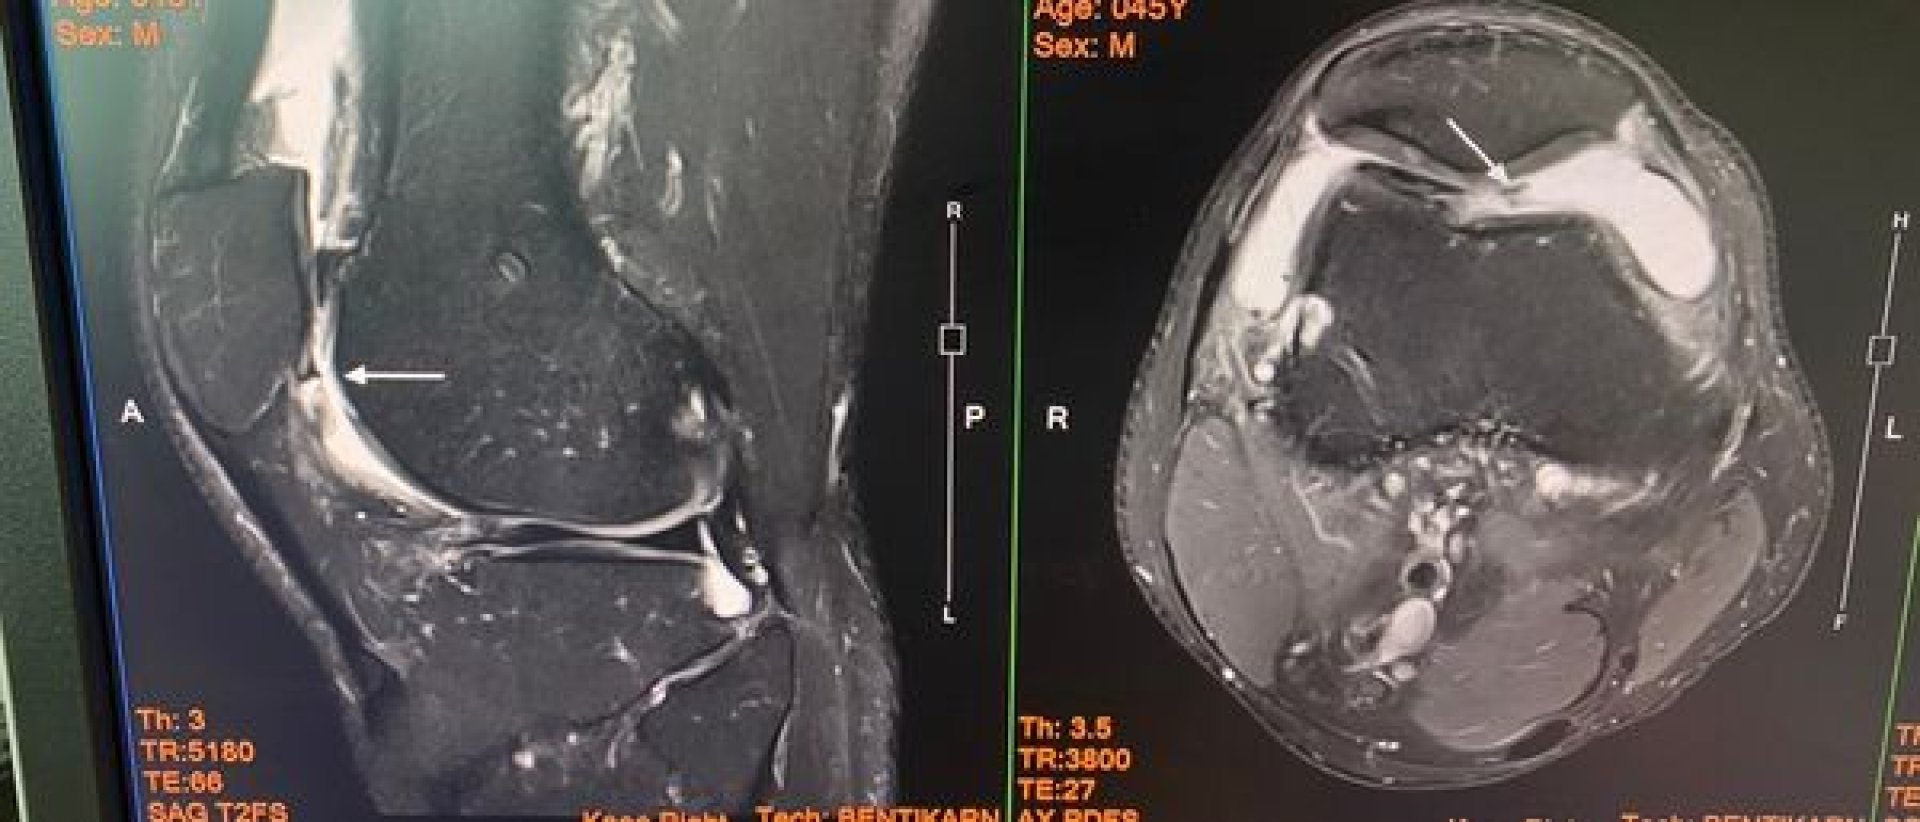

ซึ่งช่วงแรกคนไข้ทำได้ดีมากเลยครับ กลับไปเตะบอลได้หลายเดือน แต่พอเริ่มเตะได้ก็เตะมากขึ้นเวลาในการออกกำลังกล้ามเนื้อน้อยลง กลับมาบวมอักเสบอีกครั้งนึง เลยตัดสินใจส่งคนไข้ไป mri เพื่อดูความเสียหายของผิวข้อตามภาพประกอบ ตรงลูกศรจะเห็นว่า ผิวข้อเสียหายค่อนข้างเยอะ ทะลุลึกพอสมควรเลย รวมถึงมีตัวกระดูกอ่อนผิวข้อมีการหลุด แล้วคาขัดอยู่ในข้อด้วย ซึ่งอาจจะเป็นสาเหตุทำให้เหยียดเข่าได้ไม่สุด